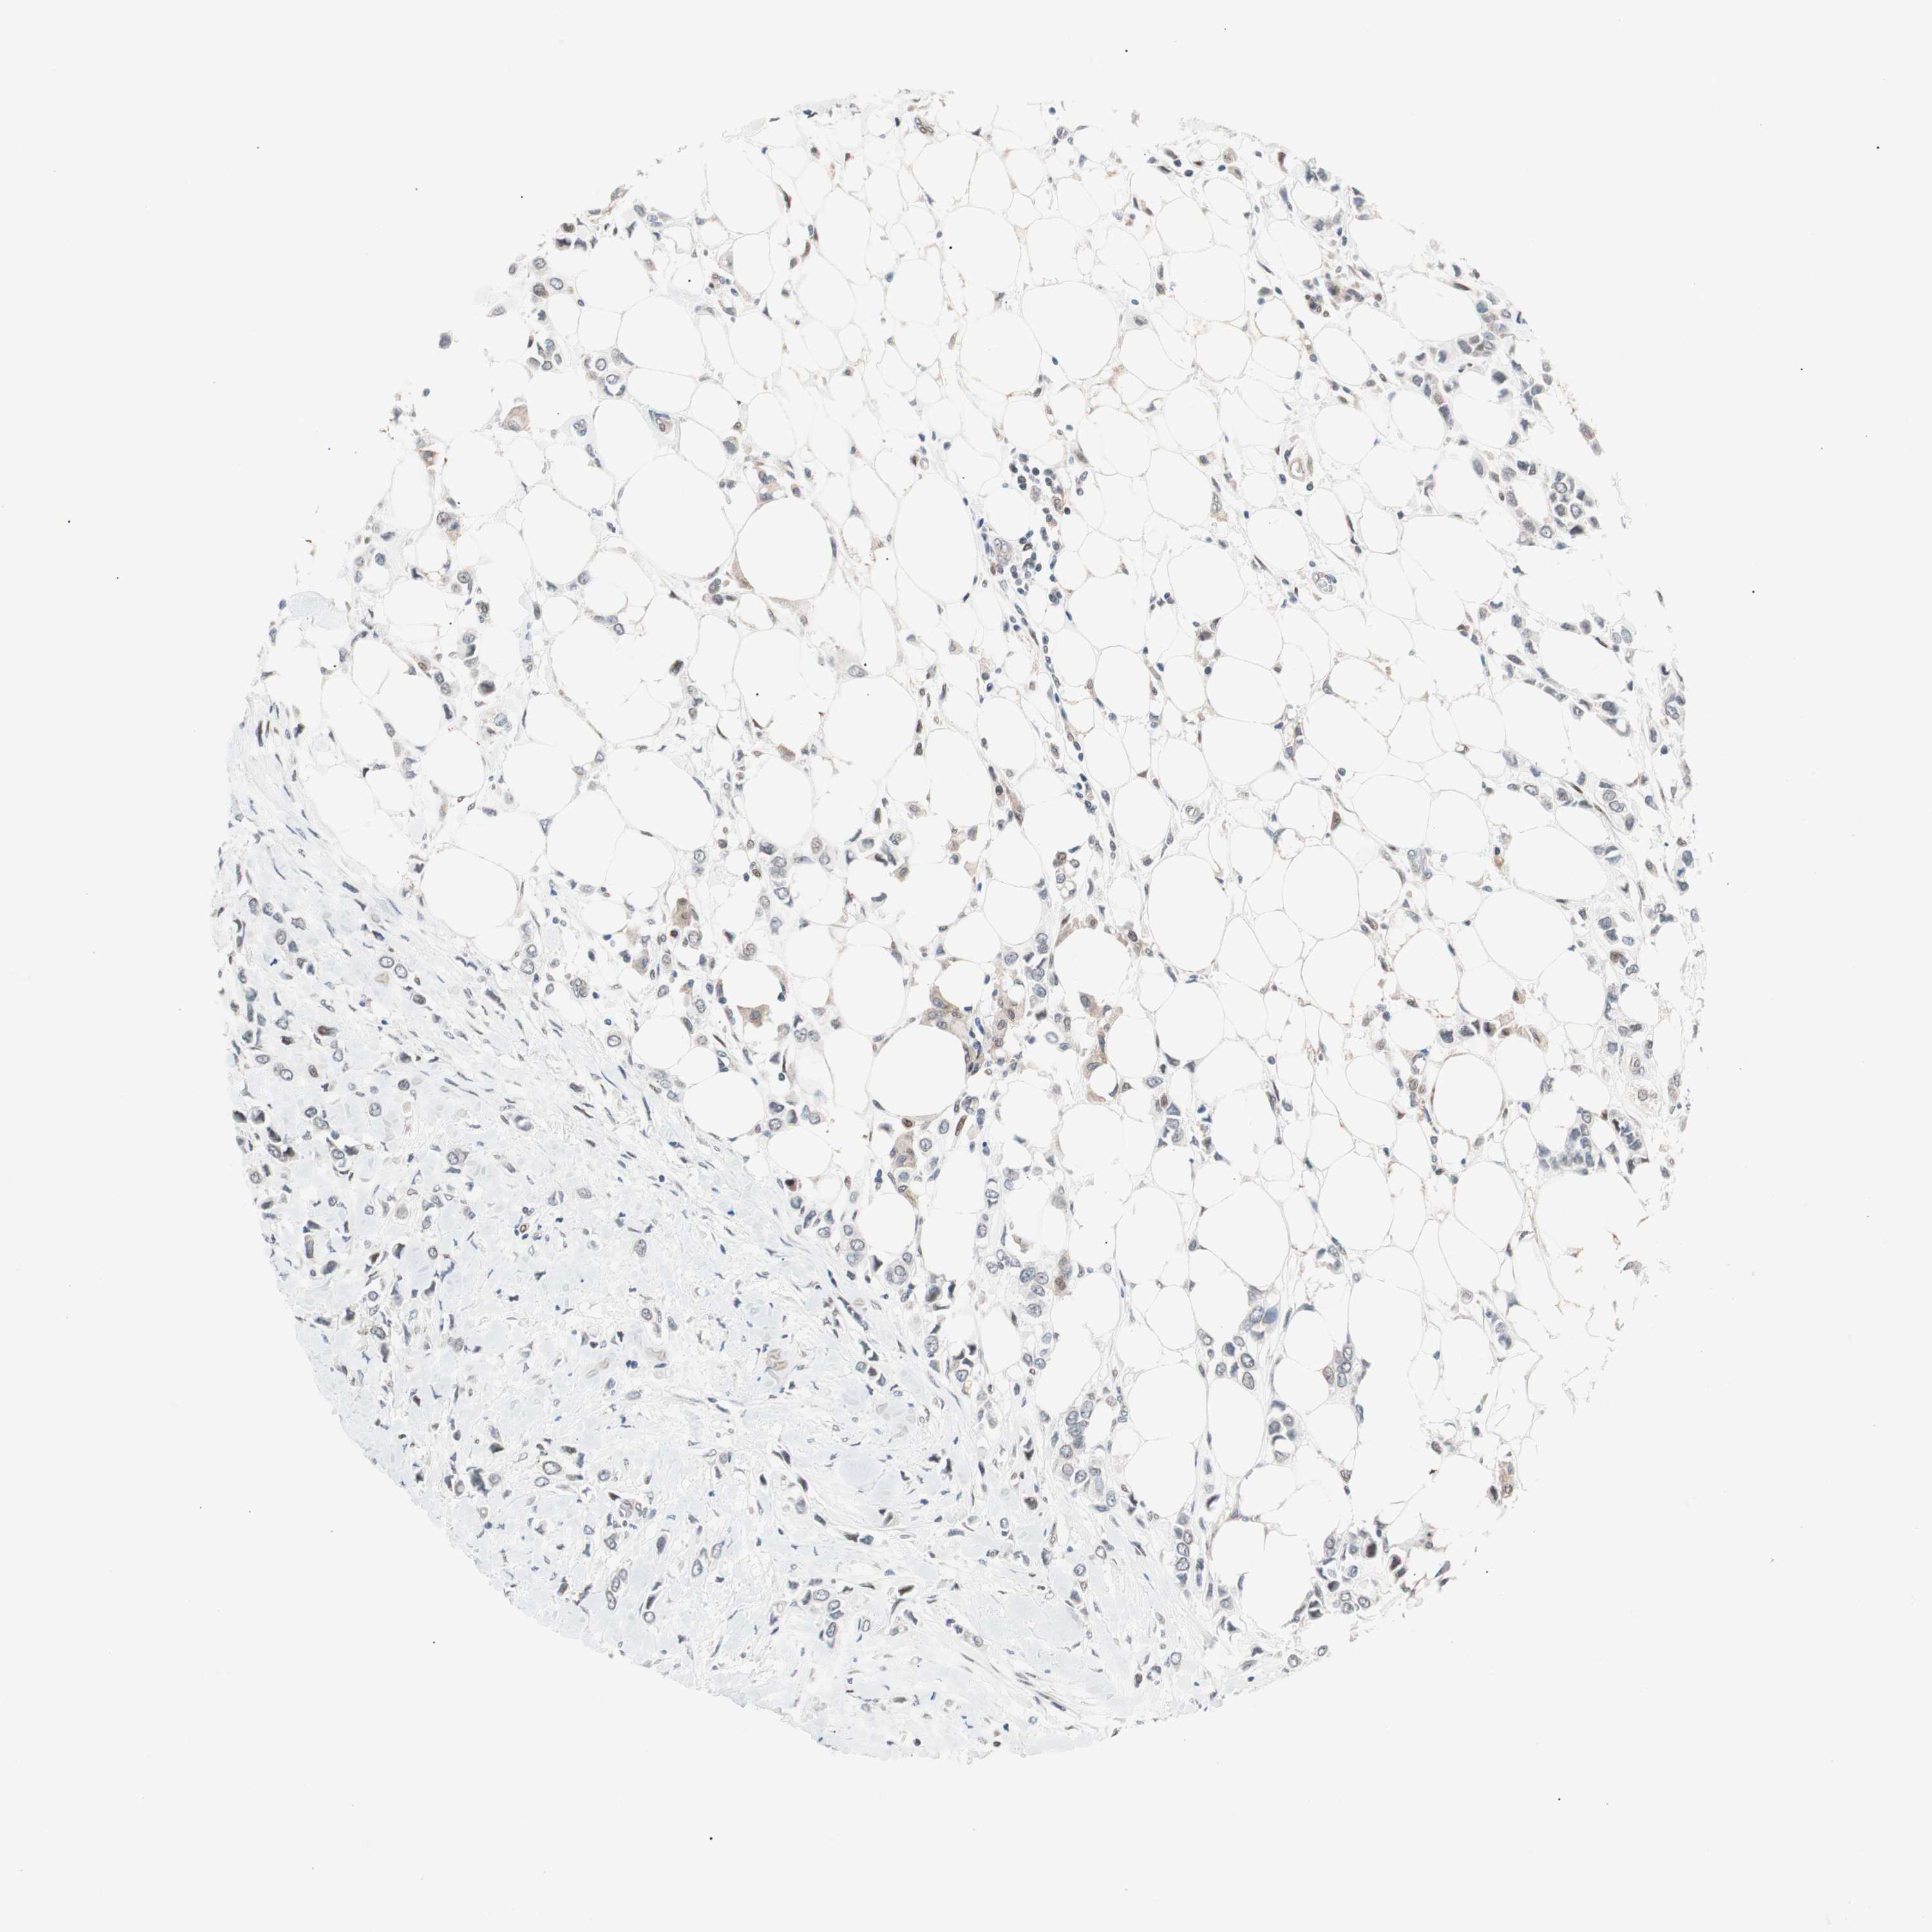

BRCA TCGA BRCA VALIDATION PROTEIN EXPRESSION

ANTIBODIES

AND

VALIDATION